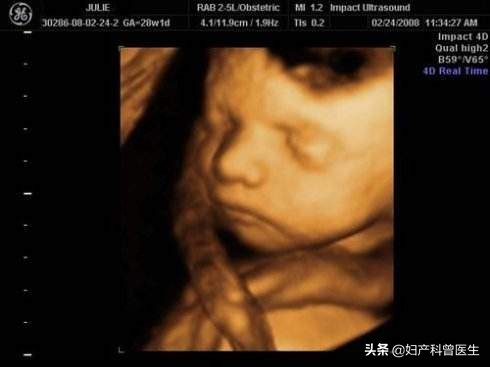

此刻,二胎妈妈娜娜她正感觉自己在经历一件后悔又恐惧的事,后悔昨天带着大宝去看电影了。#快乐寒假#想趁着寒假自己还没生二宝,好好带大宝出去看场电影,庆祝他期末考试取得优异成绩,没想到电影剧情如此跌宕起伏,看得自己一惊一乍的,她明显感觉到了肚子中的二宝踢她肚皮踢得厉害。担心二宝会有什么事,又不想让大宝扫兴,只能等到电影结束了,才匆忙赶到医院做检查,胎心监测宫内二宝的情况是没问题,但没想到做B超发现二宝脐带绕颈2周!

其实,脐带绕颈的现象在现实生活中是非常常见的事,在产科门诊或住院分娩时,几乎每天都会遇到脐带绕颈的现象。约占分娩总数的20%~25%,其中多数是脐带绕颈一周,其发生率为89%,而脐带绕颈两周发生率为11%,脐带绕颈3周及以上的就比较少见。